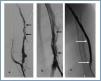

Manual catheter-directed aspiration

First, using ultrasound monitorisation, the access is threaded in the opposite direction from the arterial anastomosis. A guide wire and catheter is used to clear the obstructed segment to connect with the venous area free from thrombus. For PTFE grafts, this area is generally distal to the venous anastomosis. A safety wire is placed and we begin to aspirate thrombi with a large 7 to 9 French catheter (figures 1 and 2). Once the segment is free from thrombi, the catheter is threaded toward the arterial anastomosis and the same operation is repeated. When the access is free from thrombi, we inflate the underlying stenotic areas responsible for the thrombosis with an angioplasty balloon (figures 3 and 4). Medication during the procedure consists of midazolam as a sedative, an antibiotic (third-generation cephalosporin) and a heparin bolus with 3000-5000 IU of sodium heparin. If the patient needs dialysis immediately, the catheter introducers are left in and dialysis is performed using them. LMWH is recommended on non-dialysis days.

Figure 1.